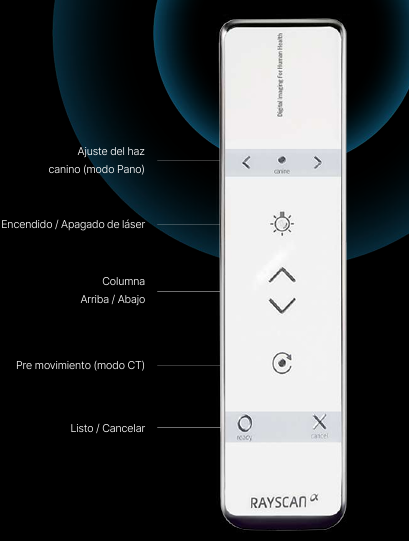

Control Remoto

Posicionamiento mejorado del paciente & ergonomía del operador.

Escaneo cómodo y sencillo

Control remoto inálambrico para una máxima comodidad

Tanto para pacientes como para profesionales sanitarios, nuestro control remoto permite operar sin esfuerzo, permitiéndoles centrarse en lo que realmente importa: el resultado del tratamiento.